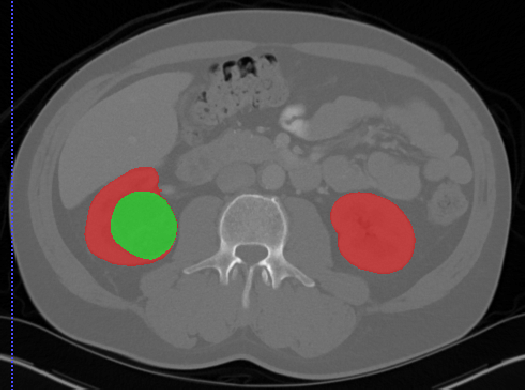

肾脏

Kits19

| 名称 | 标注内容 | 类型 | 模态 | 数量 | 标签格式 | 文件格式 | License |

|---|---|---|---|---|---|---|---|

| Kits19 | 肾脏/肾肿瘤 | 分割 |